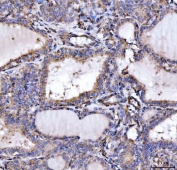

IHC staining of FFPE human colorectal adenocarcinoma tissue with SLU7 antibody. HIER: boil tissue sections in pH8 EDTA for 20 min and allow to cool before testing.